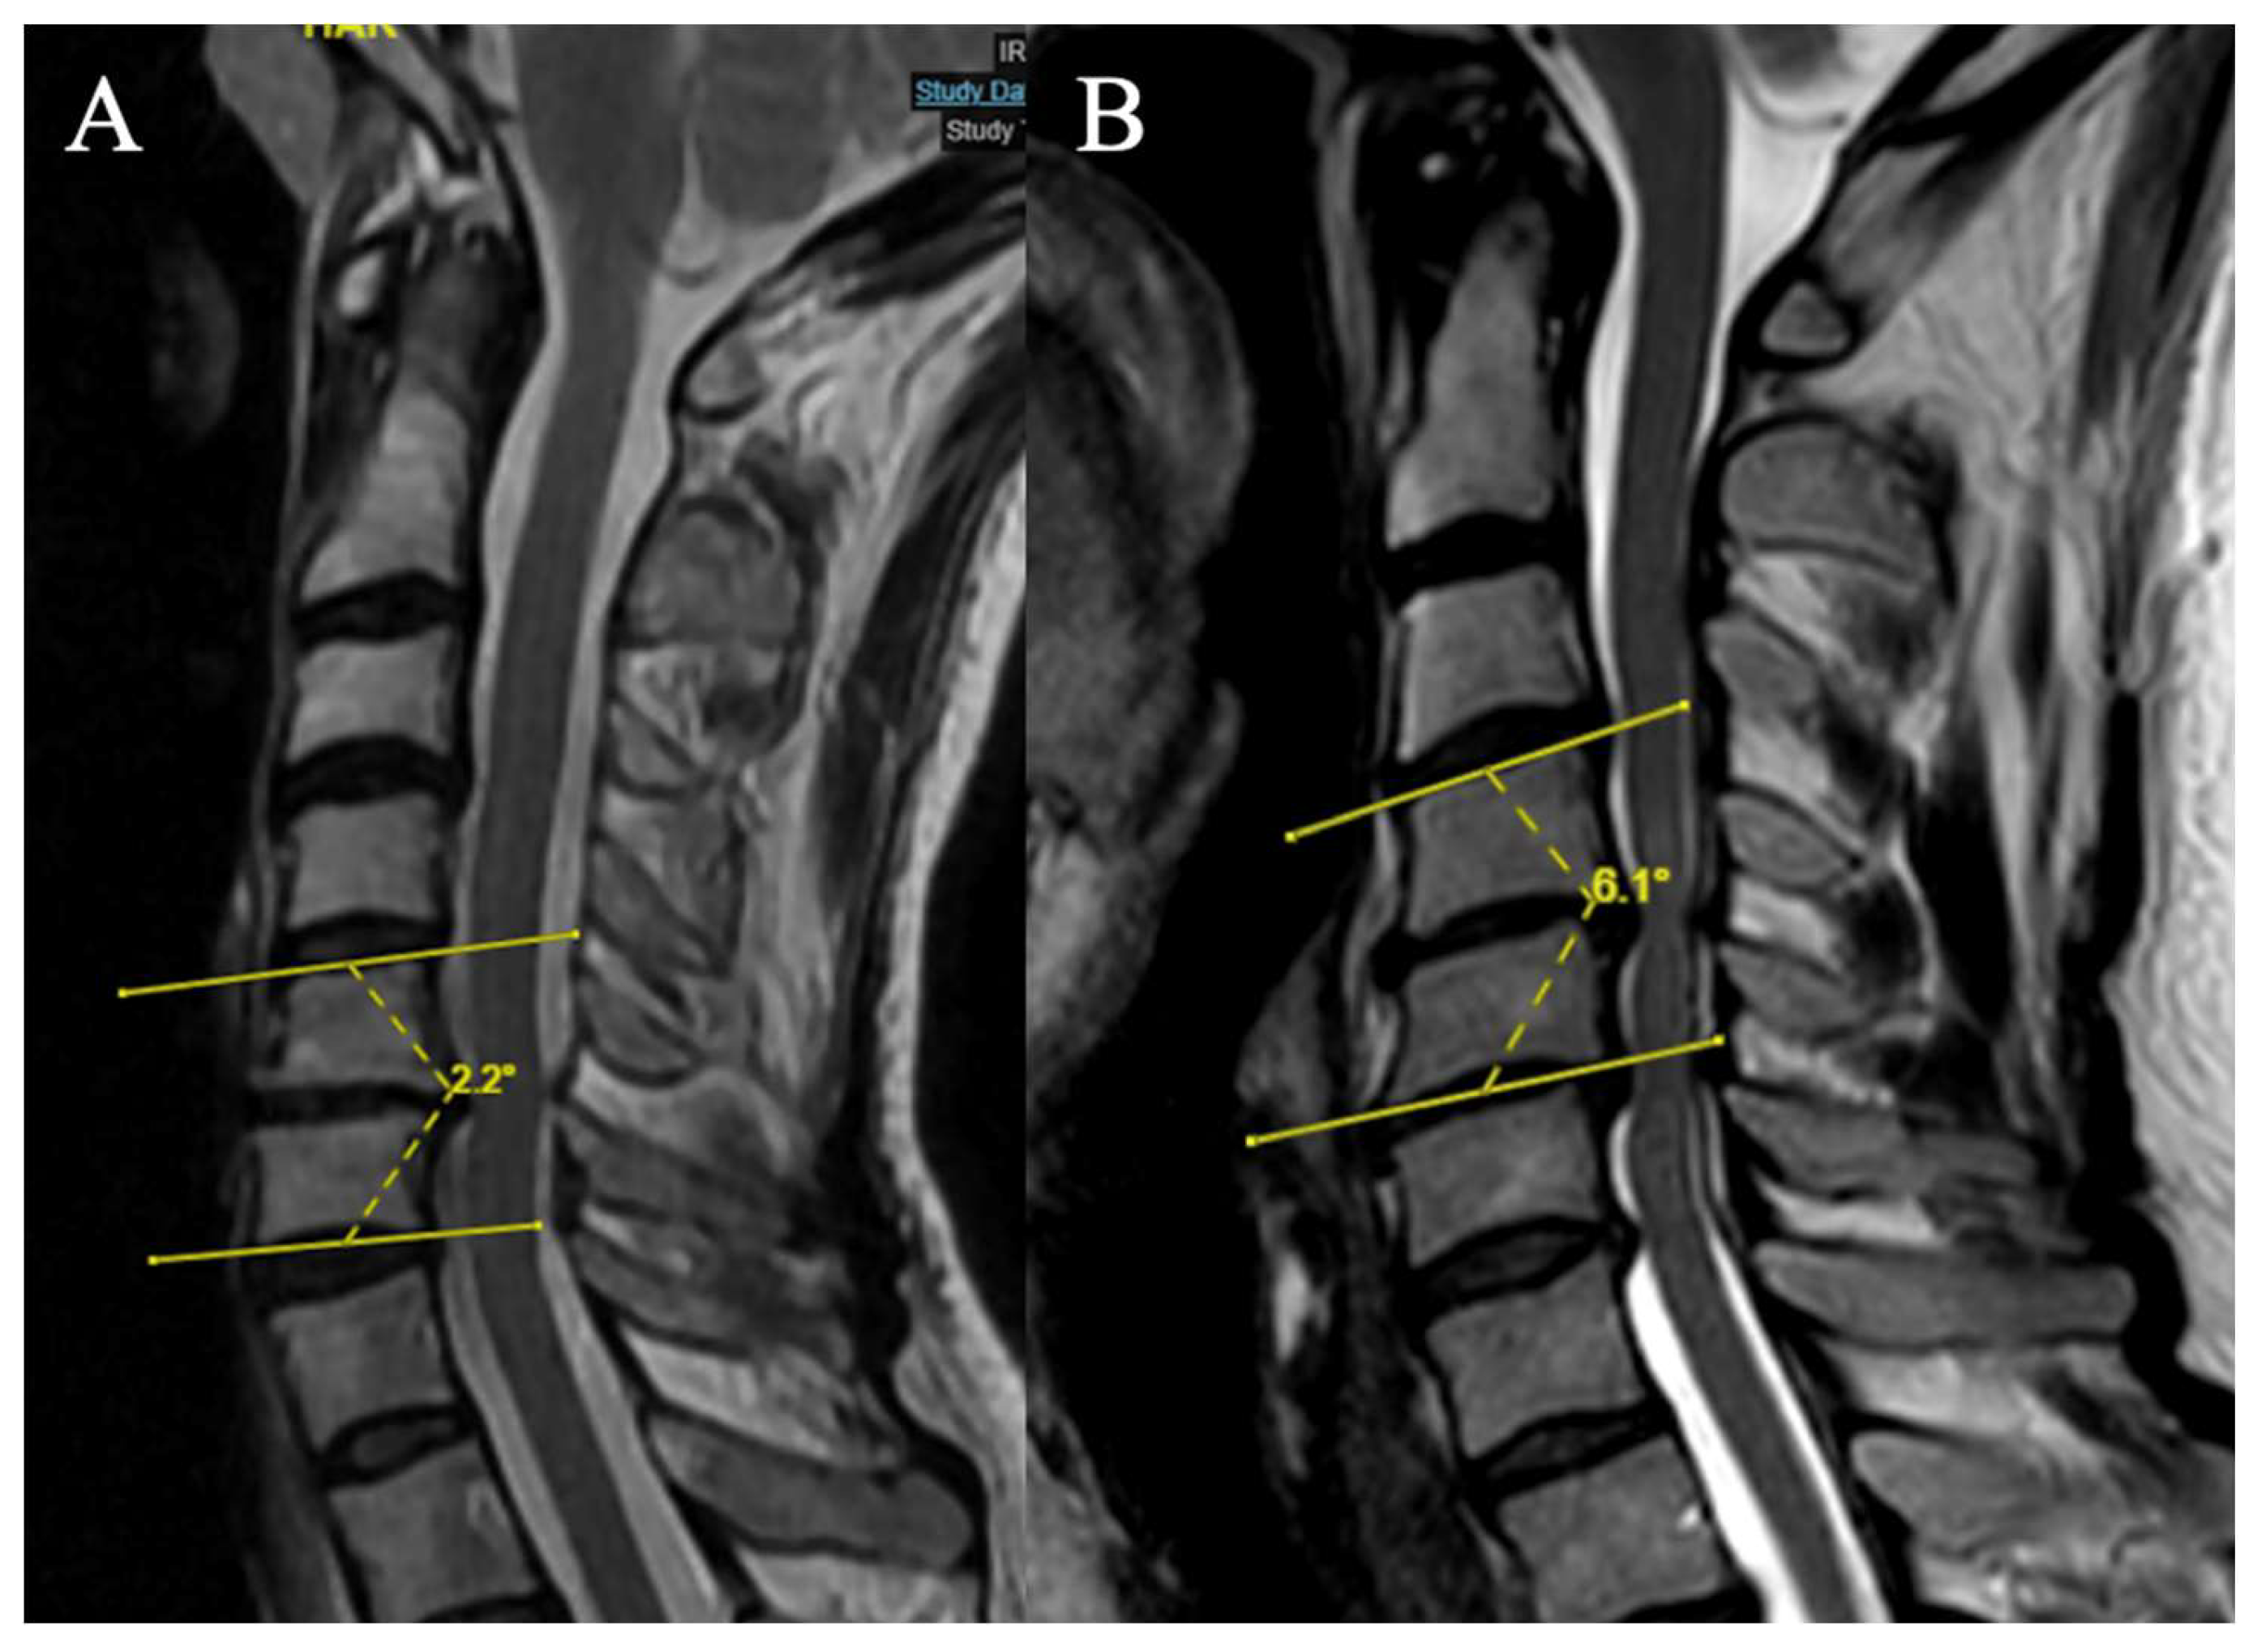

2 grades have been selected (Focal angle measured on sagittal T2-weighted MRI sequences at the level of maximum compression) (Figure 5):

(A) Lordosis or LK <4°

(B) LK ≥ 4°

Figure 5. Example of measurement of the local angle. (A) LK = 2.2°; (B) LK = 6.A°.